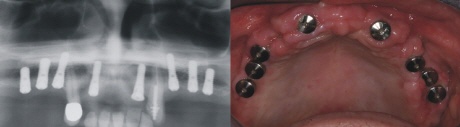

Implantation

Acht Implantate bieten im Oberkiefer eine solide Basis für eine festsitzende Brückenkonstruktion. Auf dem Bild oben rechts sieht man die Implantatkappen in der Mundhöhle. Die Implantate müssen nun wiederum 4-5 Monate im Knochen einheilen.